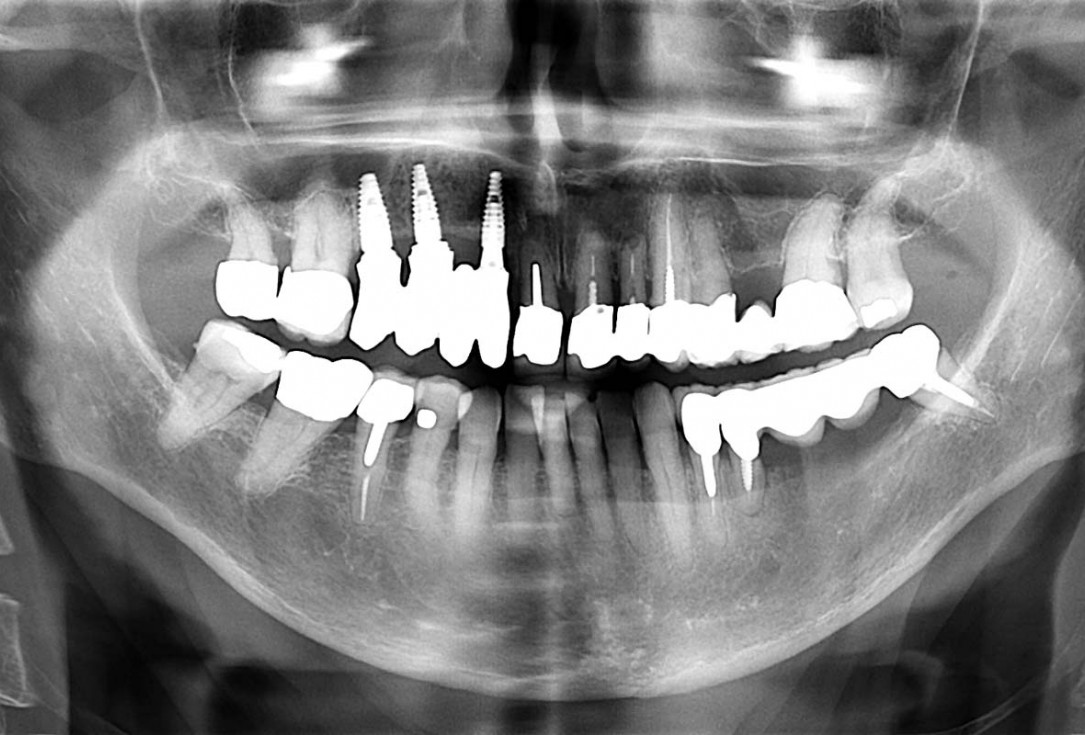

Full maxillary reconstruction with maxgraft® bonebuilder - Dr. C. Hilscher

Initial x-ray, ten years post implantationem alio loco, large peri-implant bone loss